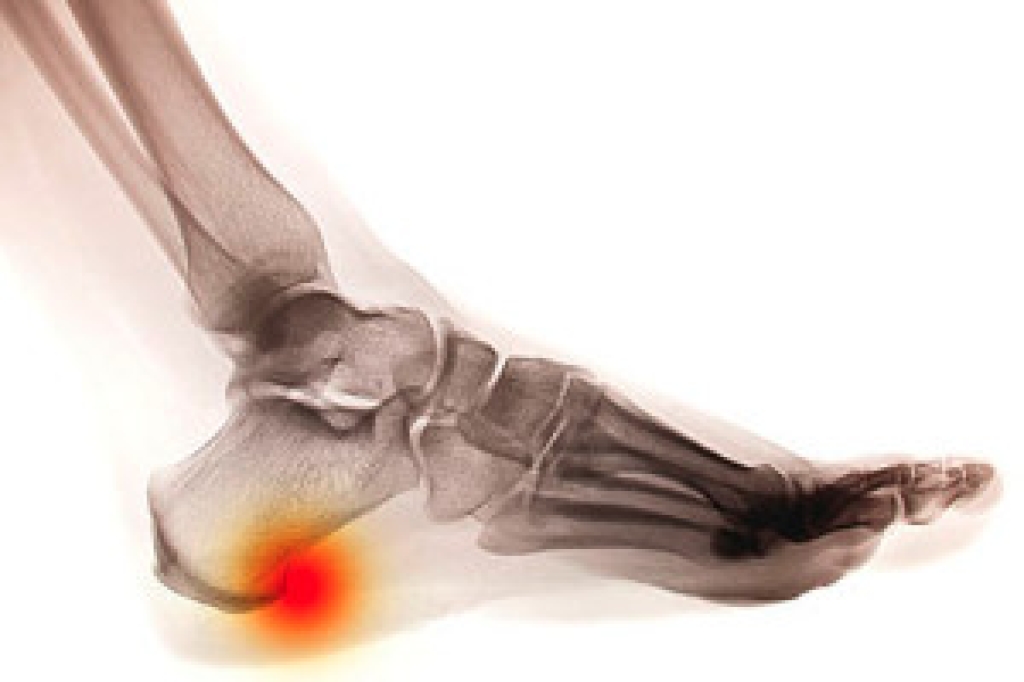

Stretching the muscles in the foot is an important part in any physical activity. Feet that are tight can lead to less flexibility and make you more prone to injury. One of the most common forms of foot pain, plantar fasciitis, can be stretched out to help ease the pain. Stretching can not only ease pain from plantar fasciitis but also prevent it as well. However, it is important to see a podiatrist first to determine if stretching is right for you. Podiatrists can also recommend other ways to stretch your feet. Once you know whether stretching is right for you, here are some excellent stretches you can do.